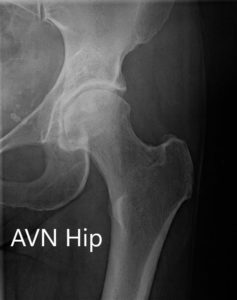

Imaging revealed osteoarthritic changes of the left hip with an AVN lesion that involves 60% of the femoral head. An MRI was obtained which revealed left femoral head avascular necrosis without overt subchondral collapse.

X-ray showing the AP view of the pelvis with both hip joints.

X-ray showing the AP and frog-legged lateral views of the left hip joint.